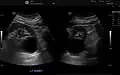

Simple renal cyst.jpg

Simple renal cyst